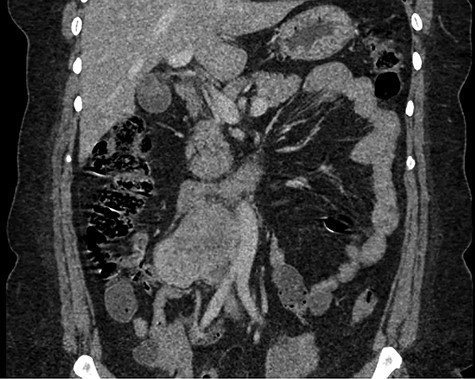

Abdominal CT scan demonstrating IVC lesion that partially encircles the aorta.

The patient had a body mass index of 40, so combined with her presentation, age and gender. The presumptive diagnosis was of gallbladder pathology, which prompted an abdominal ultrasound. Ultrasound revealed a large 7.7 × 6.3 × 7.2 cm heterogenous, hypoechoic masslike lesion overlying the IVC (Fig 1). Abdominal CT was performed, which revealed an 8.9 × 7.9 × 9 cm multilobulated, heterogeneous soft tissue mass in the right hemiabdomen, encasing the IVC and partially encasing the distal abdominal aorta (Figs. 2–4). CT-guided biopsy was performed, which revealed an LMS.